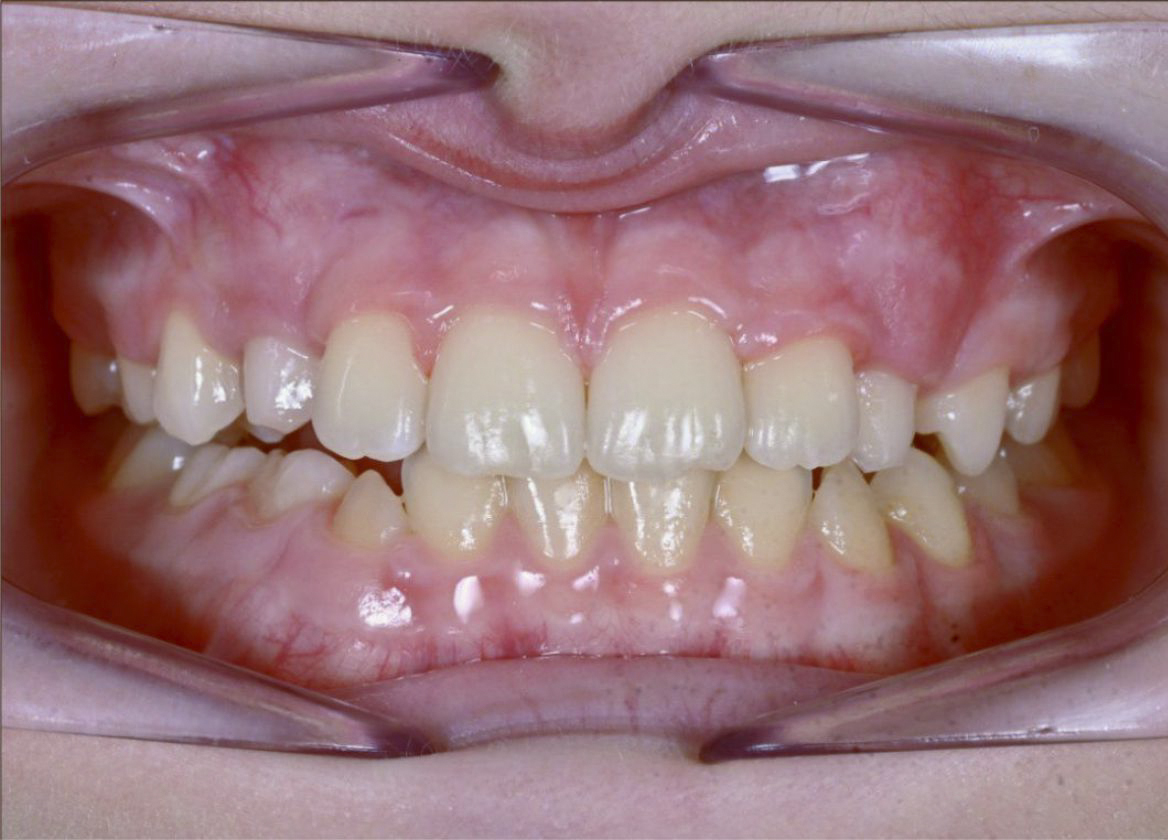

У меня никогда не смыкались зубы полностью и бепокоили клыки. Решила обратиться за консультацией к ортодонту. В завершении лечения понимаю, что это было самым моим лучшим решением-начать лечение на брекет-системе!